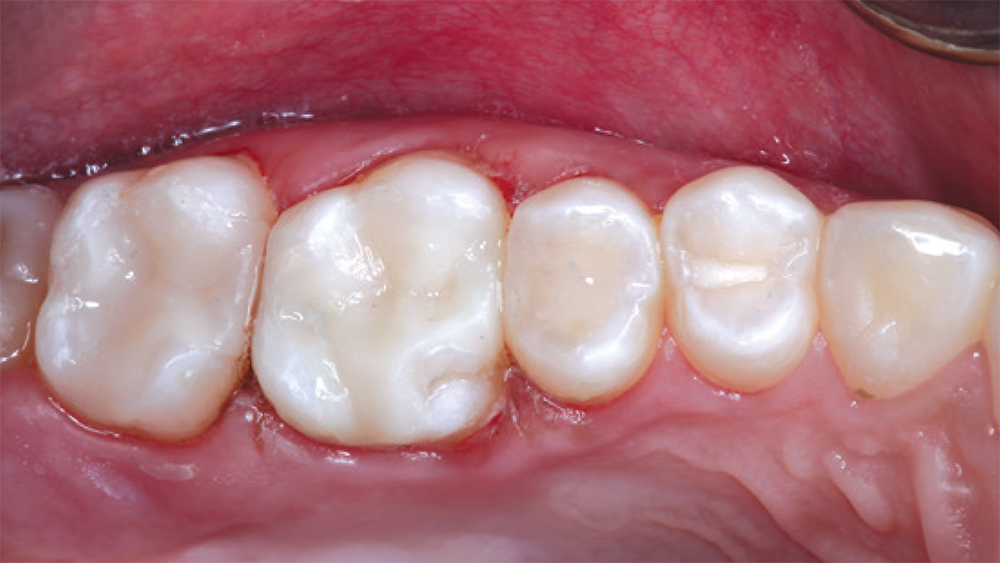

teeth #2

teeth #3

patient's fillings on teeth #2 and #3

In this case, the patient’s fillings on teeth #2 and #3 were removed and the teeth were prepared. During the same appointment, the doctor scanned the patient’s teeth and fabricated onlays from CAMouflage NOW milling blocks using the glidewell.io In-Office Solution. The onlays were delivered following a scientifically validated bonding protocol, maximizing the longevity of the nanohybrid composite restorations.